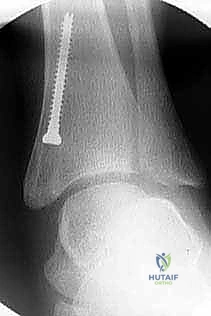

2. التصوير الشعاعي المتقدم:

لا يكتفي الدكتور هطيف بالفحص السريري، بل يتم إجراء صور أشعة سينية (X-rays) للقدم والكاحل أثناء وقوف الطفل (تحمل الوزن). يتم قياس زوايا دقيقة جداً لتقييم مدى الانحراف، مثل زاوية الساق والعقب (Tibiocalcaneal angle) وزوايا المفاصل الأخرى.

تُعد تقنية "تعديل النمو الموجه" (Guided Growth / Hemi-epiphysiodesis) واحدة من أعظم الابتكارات في جراحة عظام الأطفال الحديثة. بدلاً من إجراء جراحات قطع عظمي كبرى ومعقدة (Osteotomies) تتطلب فترة تعافي طويلة وجبساً لشهور، تعتمد هذه التقنية على مبدأ عبقري: تسخير قوة نمو الطفل الطبيعية لتصحيح التشوه.

كيف تعمل التقنية؟

يشبه الأمر تماماً تقويم الأسنان. يقوم الأستاذ الدكتور محمد هطيف بتركيب شريحة معدنية صغيرة جداً (تُعرف بشريحة الـ 8-Plate أو شريحة الشد) على الجانب الداخلي (الأسرع نمواً) من مركز النمو في أسفل عظمة الساق. هذه الشريحة تعمل كمكبح لطيف؛ فهي تبطئ النمو في الجانب الداخلي، بينما تسمح للجانب الخارجي بالاستمرار في النمو بشكل طبيعي. بمرور الأشهر، وبفضل استمرار نمو الطفل، "يُعدّل" الكاحل نفسه تدريجياً ويستقيم محوره تماماً.

الخطوة الرابعة: تثبيت الشريحة (8-Plate)

بمهارة فائقة، يقوم الدكتور هطيف بوضع الشريحة المعدنية المصنوعة من التيتانيوم الطبي النقي فوق مركز النمو. يتم تثبيت الشريحة باستخدام مسمارين صغيرين؛ أحدهما فوق خط النمو والآخر تحته. هذه المسامير لا تخترق مركز النمو نفسه، مما يضمن عدم تدميره.